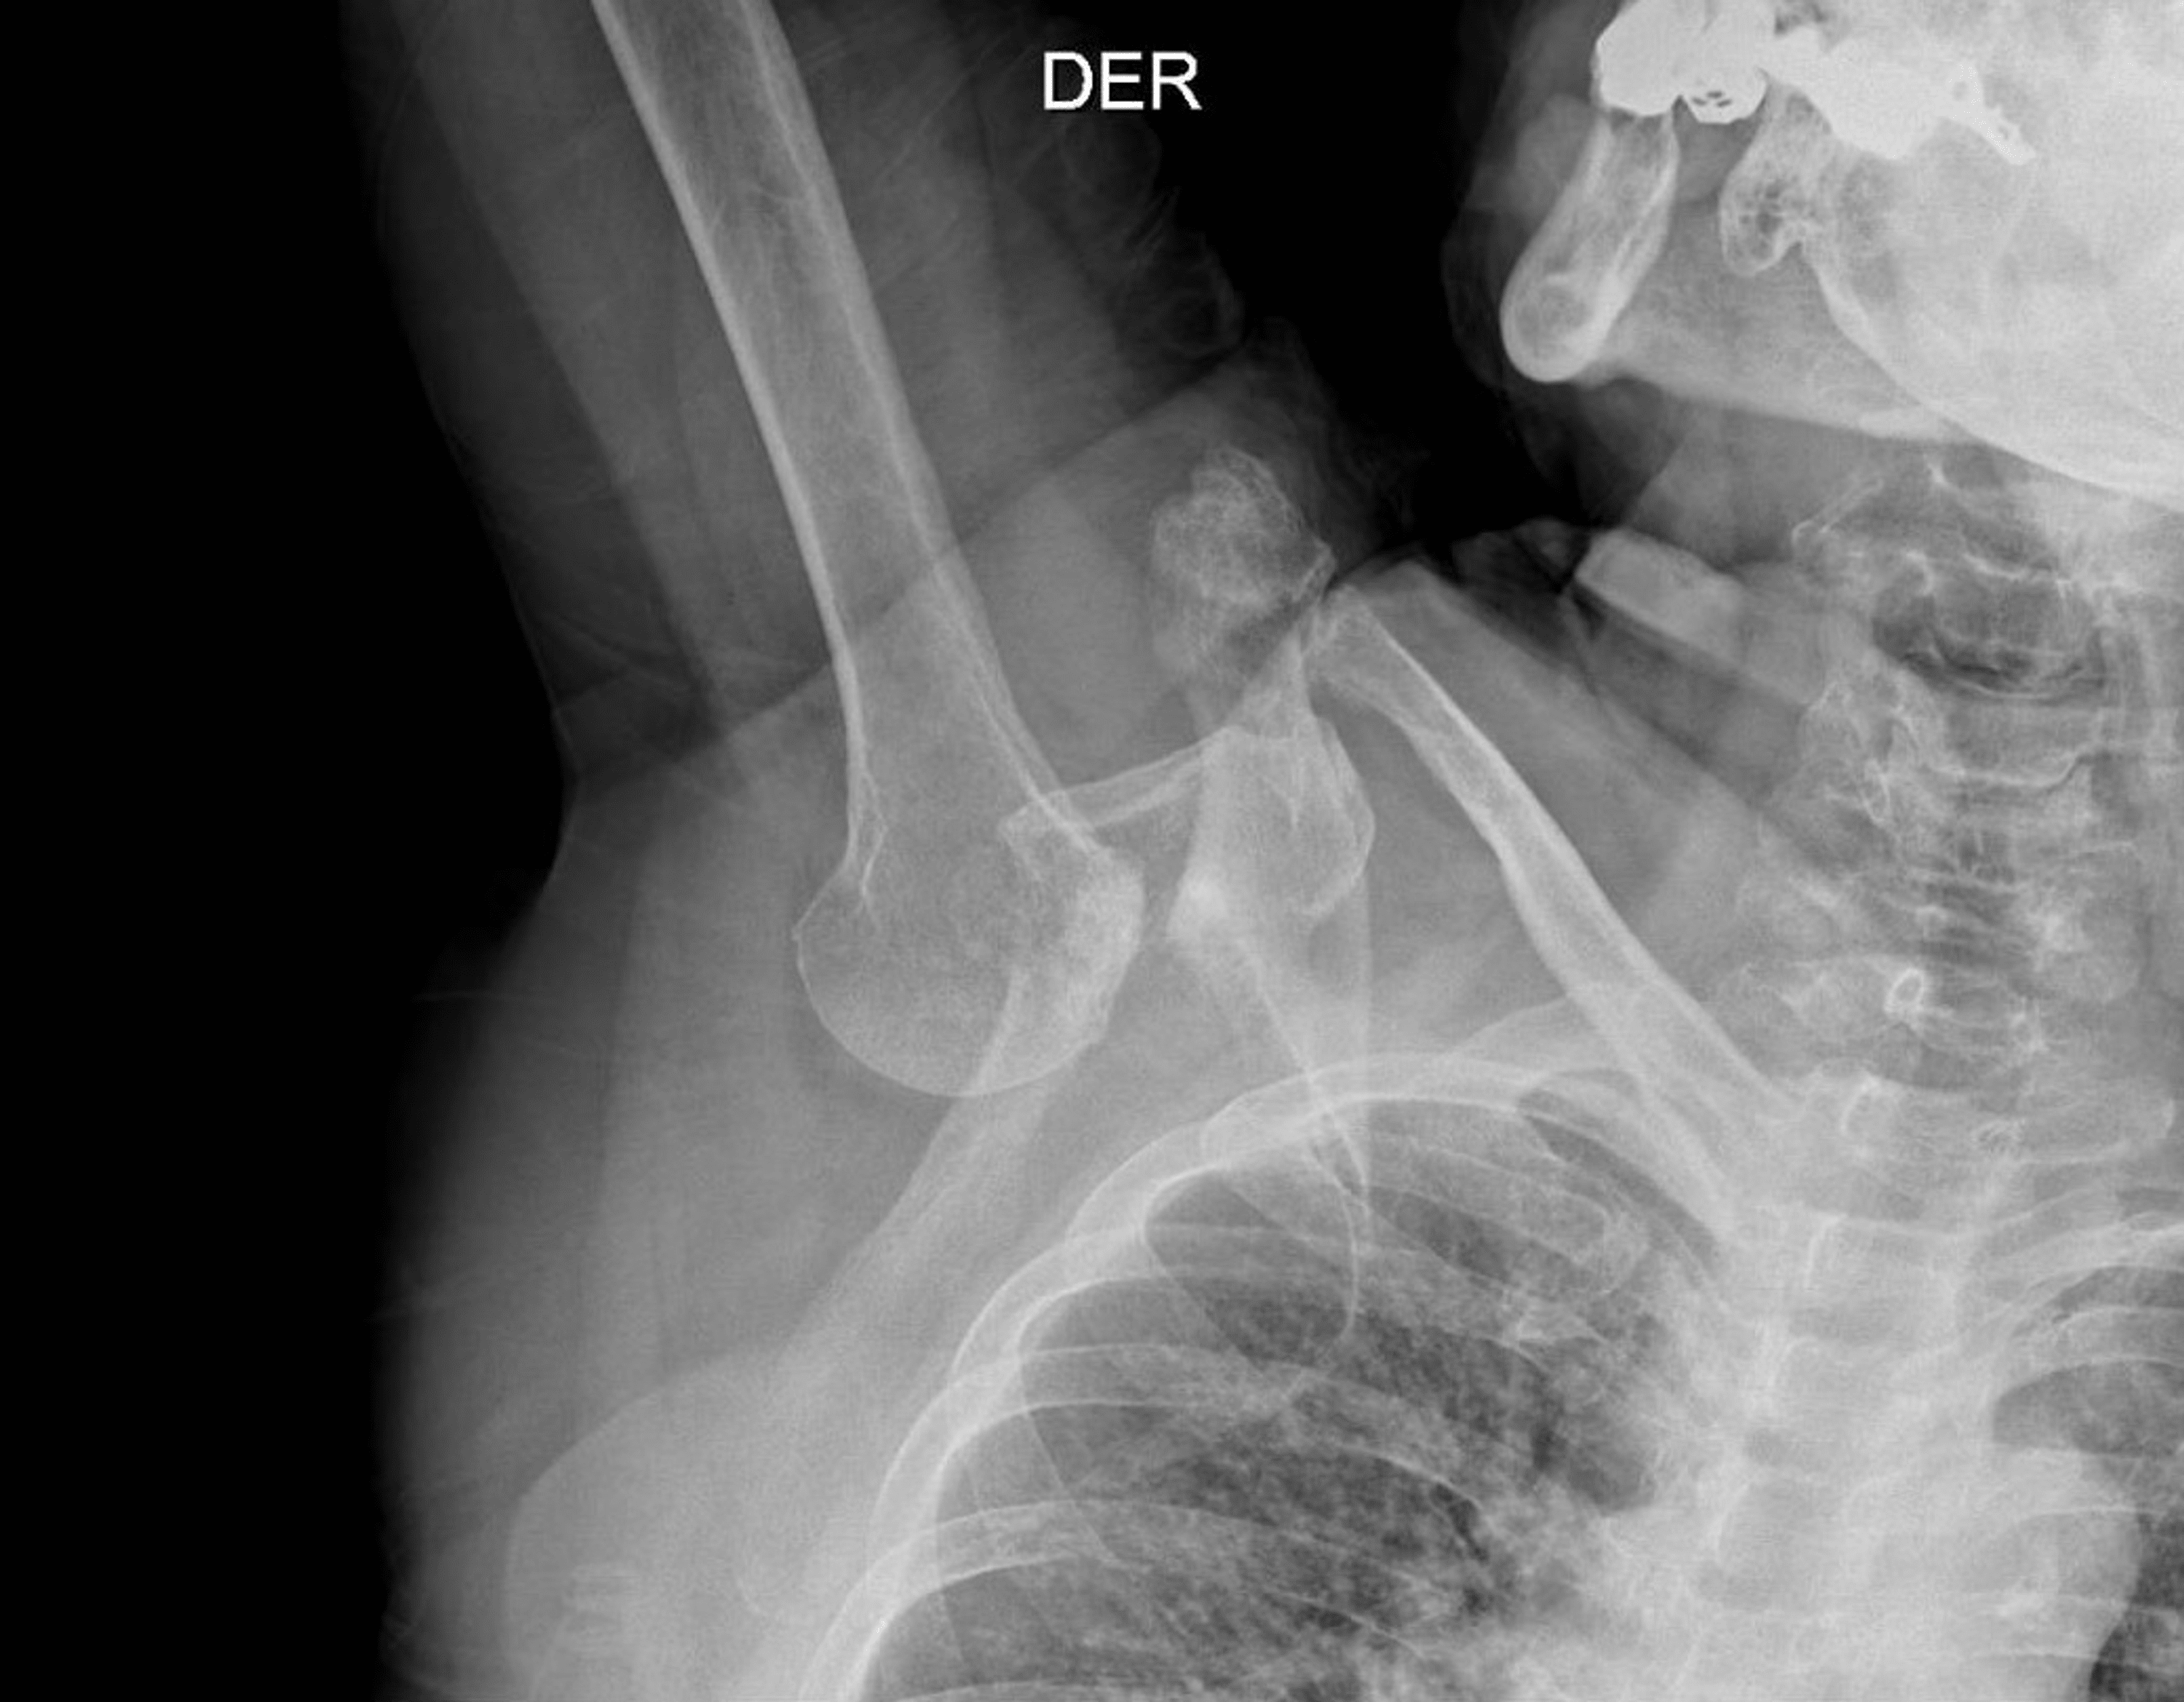

Cureus Luxatio Erecta A Case Report and Literature Review Normal Shoulder X Ray Measurements — joyce h. Shoulder mri by n seth; normal radiographic measurements of the shoulder are important in the evaluation of the osseous relationships in plain. Even though imaging trends for the shoulder continue to evolve, standard radiography. The projection demonstrates the shoulder in its natural. — the shoulder ap view is a standard projection that makes up. Normal Shoulder X Ray Measurements.